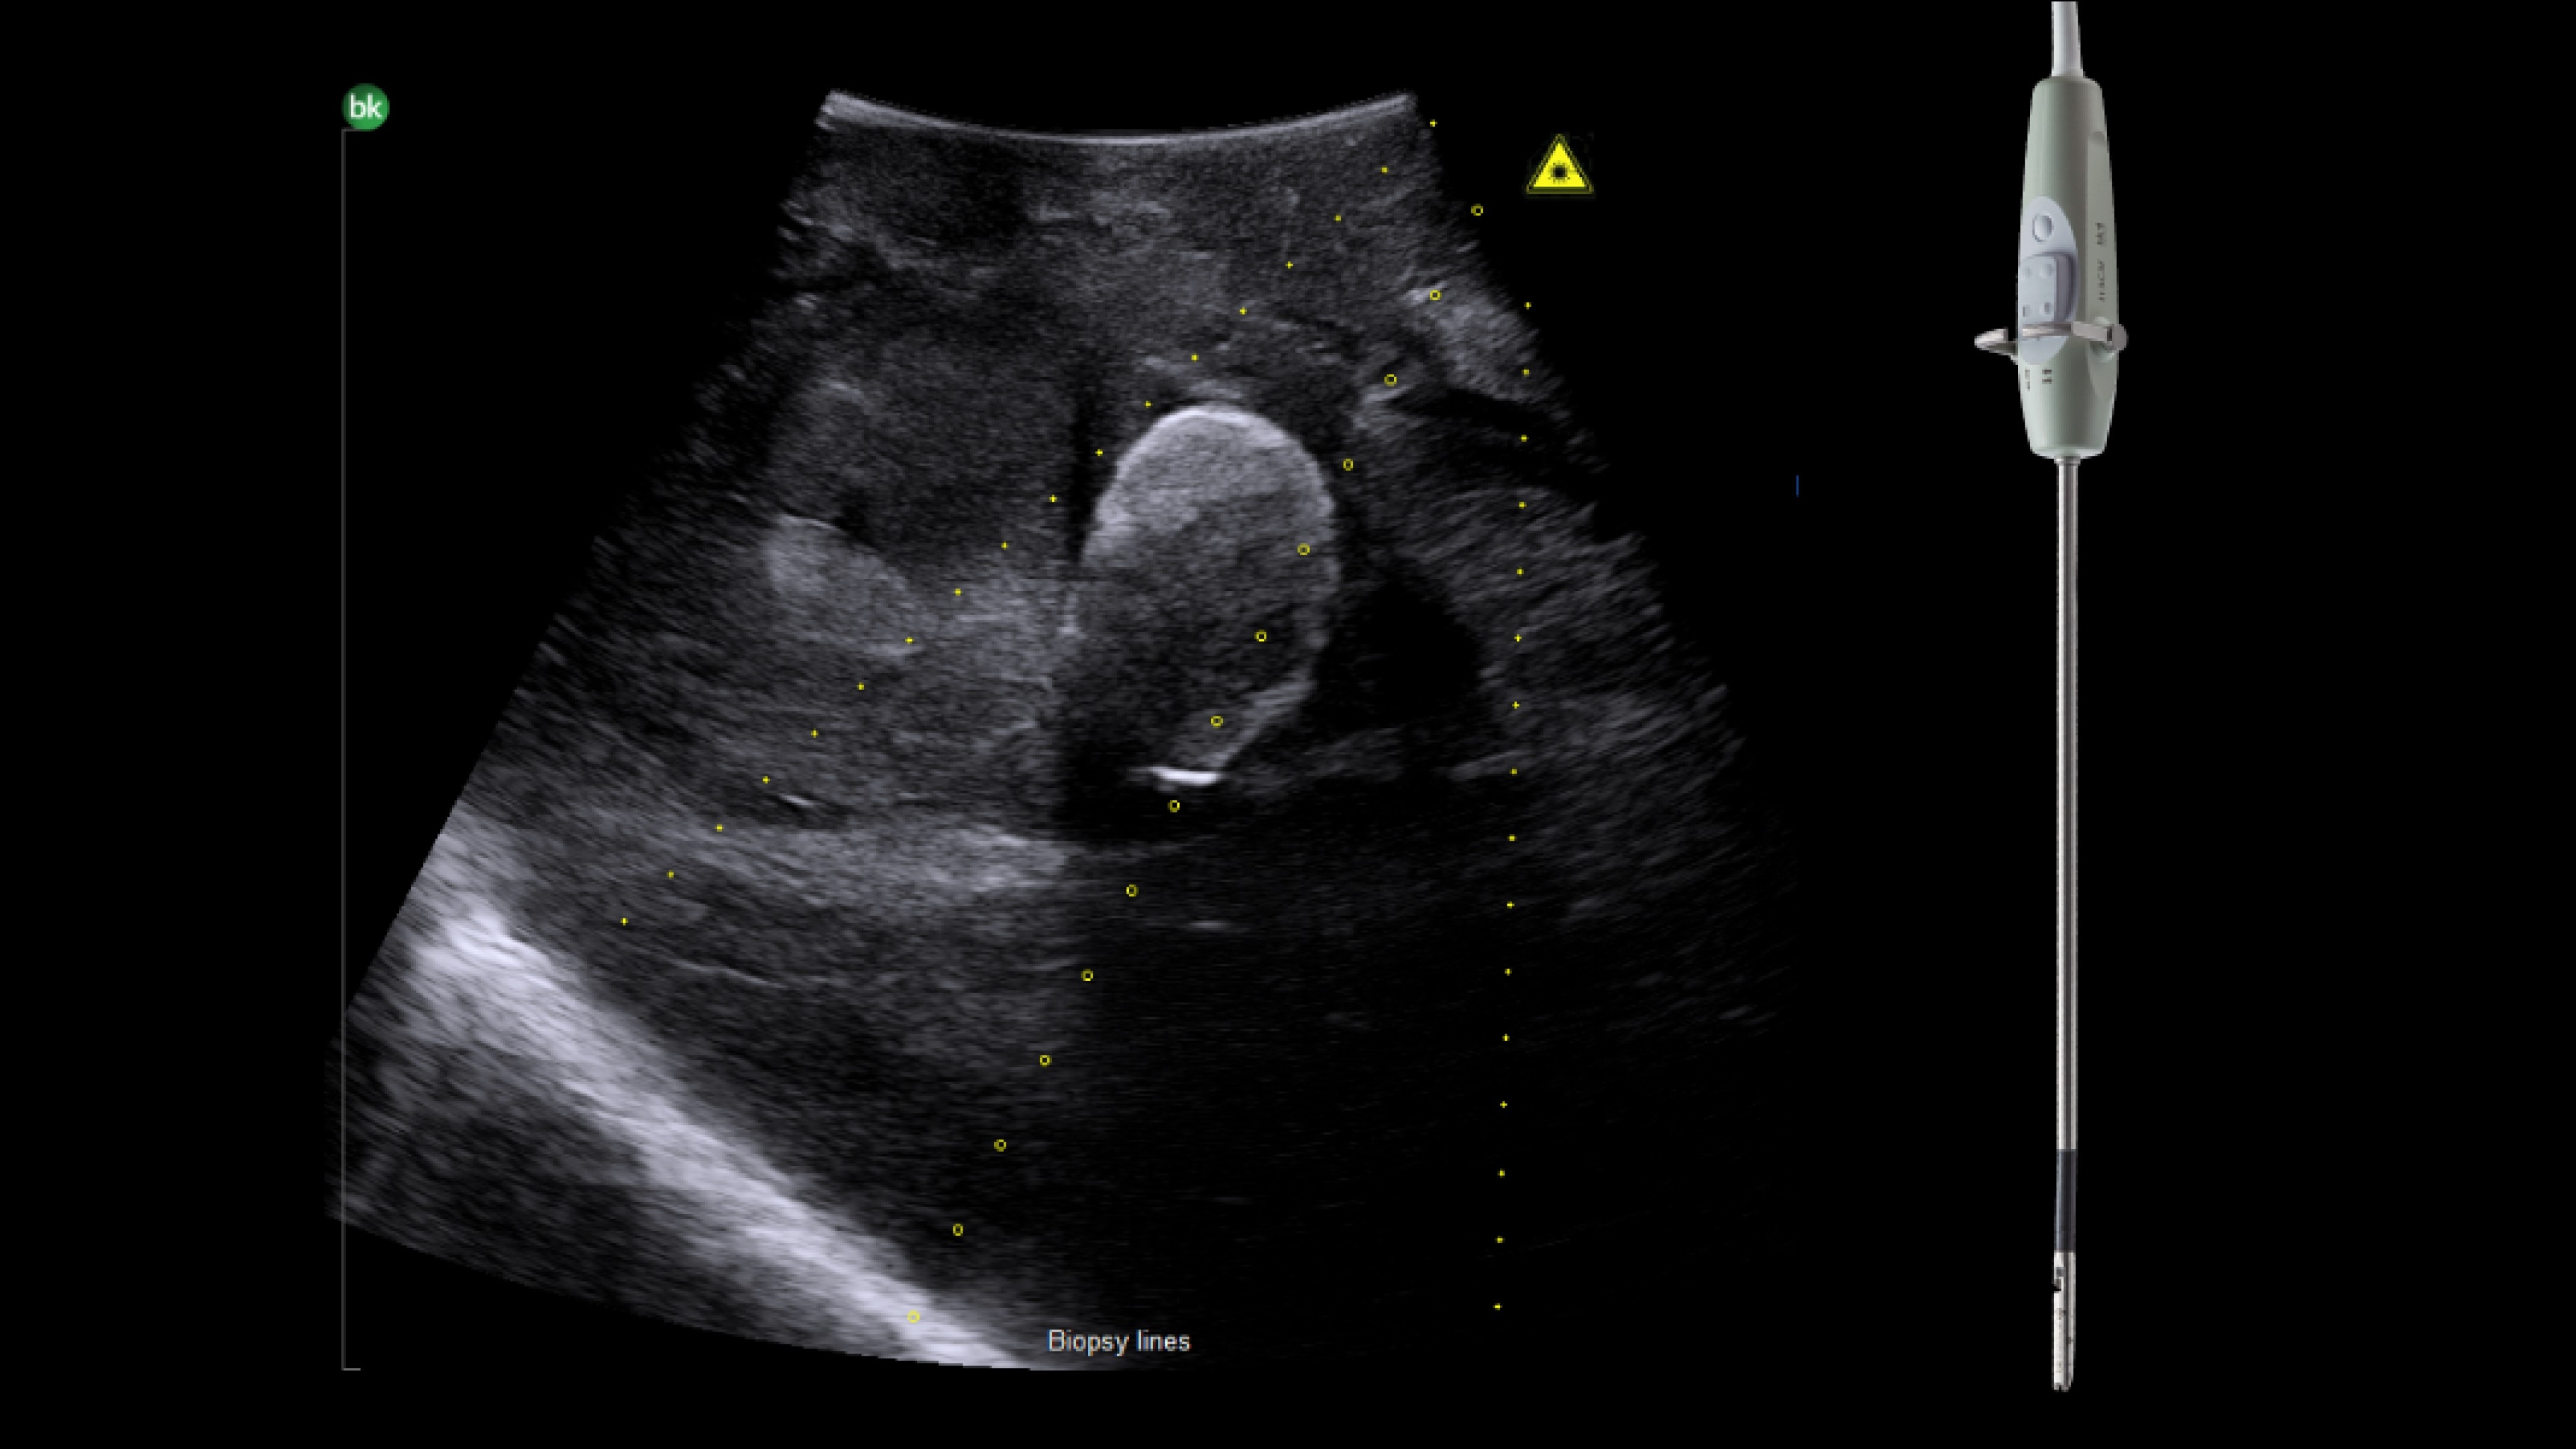

Active imaging supports liver and pancreas ablation procedures by helping you visualize lesions and blood vessels, identify healthy tissue vs. tumor, and guide and view needle placements.

Use intraoperative ultrasound to:

• Enable visualization of disease staging at the time of surgery with excellent image quality.

• Guide and view needle placements in real-time.

• Verify your planned results by assessing pre- and post-ablation images together.

Advanced Laparoscopic Transducer I13C3f*

• Plan and target tumor biopsies and ablations with patented laser technology.

• Achieve preferred insertion angle on up to two needles with proprietary channel design.